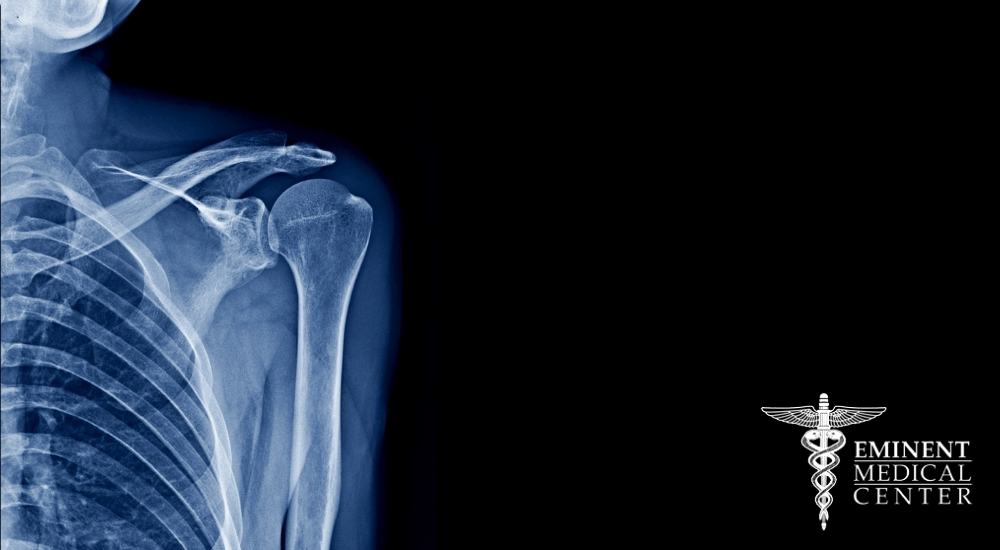

During the physical exam, your doctor will determine how much range of motion you have and identify any areas of pain. They will check how much you can move your arm on your own (active range of motion) and then gently move your arm for you to assess your passive range of motion. Imaging tests, such as X-rays or magnetic resonance imaging (MRI), may also be used to rule out other shoulder problems like arthritis or a rotator cuff tear.